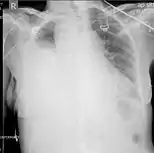

Ultrasound scan of the chest showing a left-sided hemothorax

Ultrasonography may be used to detect hemothorax and other pleural effusions. This technique is of particular use in the critical care and trauma settings as it provides rapid, reliable results at the bedside.[23] Ultrasound is more sensitive than chest x-ray in detecting hemothorax.[25] Ultrasound can cause issues in people who are morbidly obese or have subcutaneous emphysema. When CT is unavailable in the current setting or the person cannot be moved to the scan, ultrasound is used.[3]

Computed tomography (CT or CAT) scans may be useful for diagnosing retained hemothorax as this form of imaging can detect much smaller amounts of fluid than a plain chest X-ray. However, CT is less used as a primary means of diagnosis within the trauma setting, as these scans require a critically ill person to be transported to a scanner, are slower, and require the subject to remain supine.[23][26]